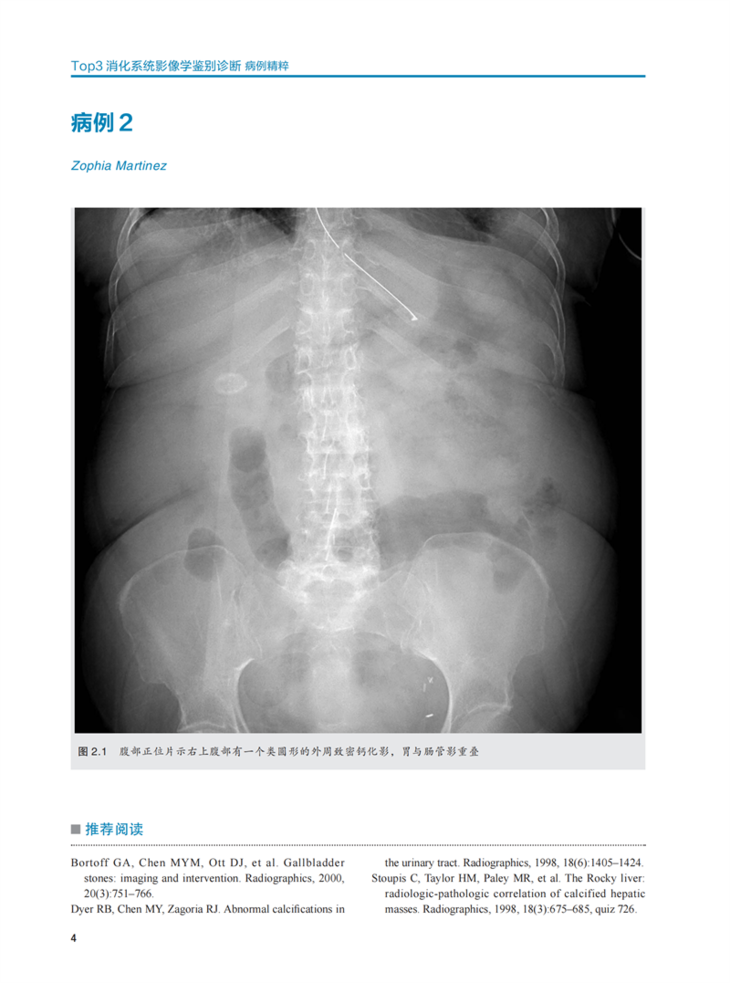

·200 幅高质量影像图片辅助诊断。

·150例精选病例,涉及X线、CT、超声、MRI、钡餐透视等成像方式。

《Top3胃肠道影像学鉴别诊断》包括肝胆、胰腺和脾脏、胃肠道、肠系膜和血管、腹壁和软组织5个部分的150个病例。与其他Top 3系列的图书一样,本书的重点是基于病例的鉴别诊断,必要的病例中还补充了X线检查方面的内容。基于特定临床病史或影像学表现的 “Top 3”鉴别诊断是临床诊治的重要参考因素,这些精心挑选的病例涵盖了所有影像学成像方式,并且进行了胃肠道成像方面高质量和全面的阐述,对培养影像学医生的诊断思维和丰富知识储备有非常重要的作用。本书可以作为住院医师和主治医师的影像快速参考书。